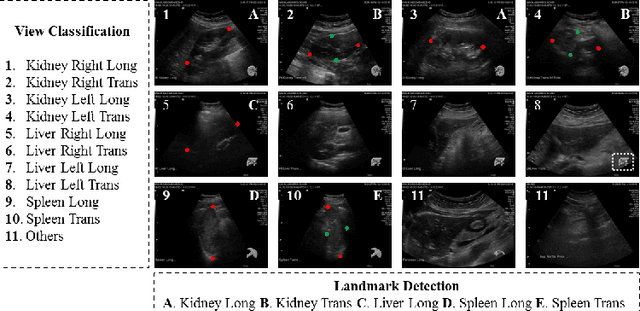

Abstract:An abdominal ultrasound examination, which is the most common ultrasound examination, requires substantial manual efforts to acquire standard abdominal organ views, annotate the views in texts, and record clinically relevant organ measurements. Hence, automatic view classification and landmark detection of the organs can be instrumental to streamline the examination workflow. However, this is a challenging problem given not only the inherent difficulties from the ultrasound modality, e.g., low contrast and large variations, but also the heterogeneity across tasks, i.e., one classification task for all views, and then one landmark detection task for each relevant view. While convolutional neural networks (CNN) have demonstrated more promising outcomes on ultrasound image analytics than traditional machine learning approaches, it becomes impractical to deploy multiple networks (one for each task) due to the limited computational and memory resources on most existing ultrasound scanners. To overcome such limits, we propose a multi-task learning framework to handle all the tasks by a single network. This network is integrated to perform view classification and landmark detection simultaneously; it is also equipped with global convolutional kernels, coordinate constraints, and a conditional adversarial module to leverage the performances. In an experimental study based on 187,219 ultrasound images, with the proposed simplified approach we achieve (1) view classification accuracy better than the agreement between two clinical experts and (2) landmark-based measurement errors on par with inter-user variability. The multi-task approach also benefits from sharing the feature extraction during the training process across all tasks and, as a result, outperforms the approaches that address each task individually.